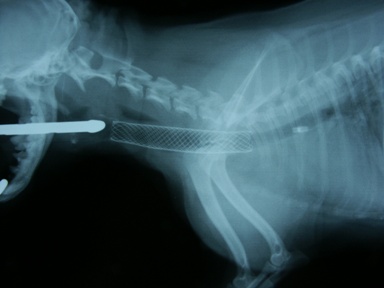

処置および経過:Tチューブ(8mm)留置し救急処置(図14)。Vet Stent-Tracheaに交換(図15)

図14 症例3の初診日、Tチューブ留置。

図15 症例3の第79病日Vet Stent-Tracheaに交換。